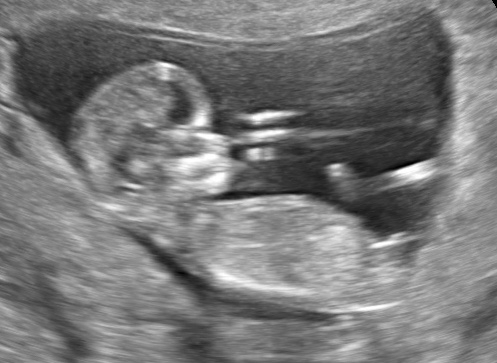

16 weken